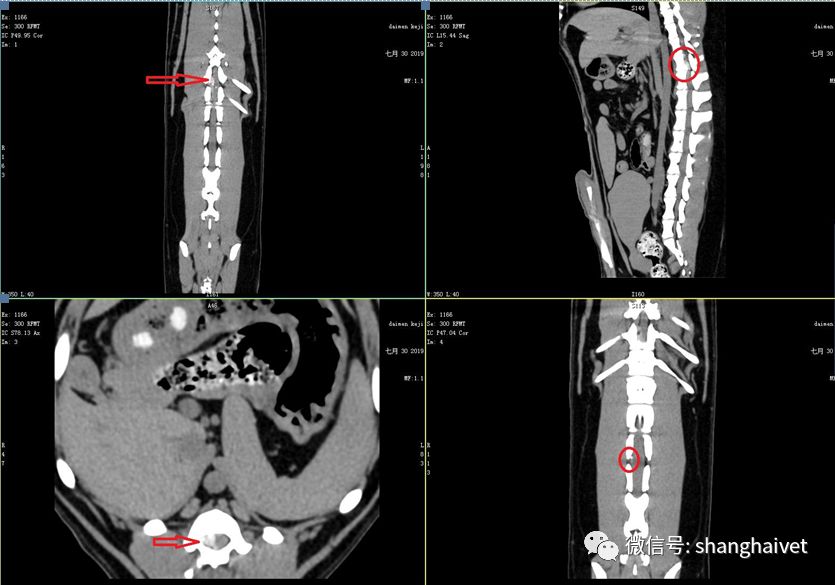

▲CT扫描结果

几分钟后,检查结果显示L3-L4段椎间盘间隙变小,在T12-T13椎间盘背侧可见明显的矿化椎间盘物质,部分物质进入椎管,在椎管的右侧对脊椎有明显的压迫。L3-L4椎间盘横断面见右侧少量矿化的椎间盘,在椎管一侧,未对脊髓有明显压迫。胸腰椎各椎体未见异常,椎体周围软组织密度正常,未见团块侵入。

随着检查的进行,导致瘫痪的“凶手”渐渐浮出水面。想要彻底查出原因,还需要借助MRI进行神经检查。